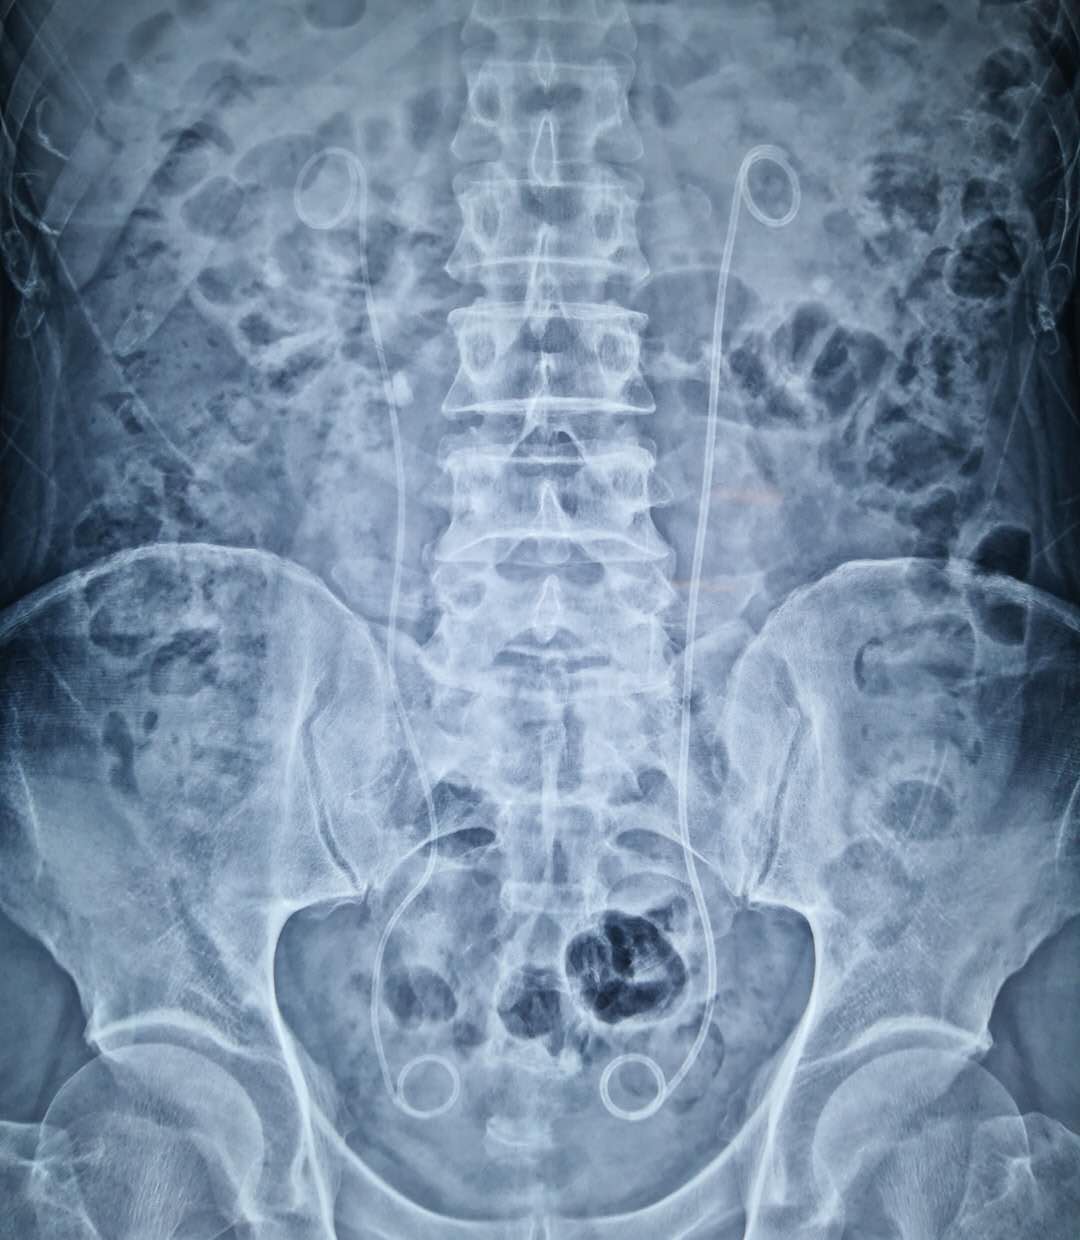

想必很多泌尿外科手术患者对于“双J管”并不陌生。双"J"管学名"输尿管支架管",两端的环圈分别置于肾盂和膀胱内,起到固定支撑输尿管,解除输尿管炎症、水肿造成的暂时性梗阻,预防术后吻合口漏和输尿管狭窄,以及输尿管结石的促排作用,被广泛运用于泌尿外科临床;因其形似猪尾巴,故俗称"猪尾巴引流管"。今天为大家科普有关留置“双J管”的注意事项。